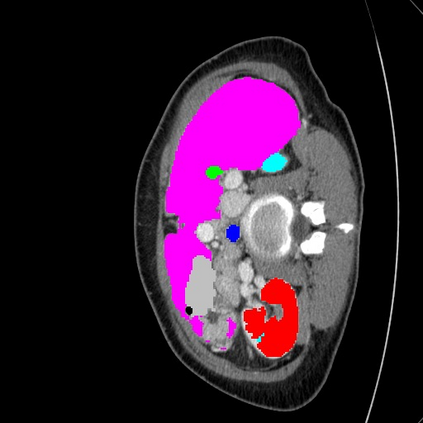

Transformers have made remarkable progress towards modeling long-range dependencies within the medical image analysis domain. However, current transformer-based models suffer from several disadvantages: (1) existing methods fail to capture the important features of the images due to the naive tokenization scheme; (2) the models suffer from information loss because they only consider single-scale feature representations; and (3) the segmentation label maps generated by the models are not accurate enough without considering rich semantic contexts and anatomical textures. In this work, we present CASTformer, a novel type of generative adversarial transformers, for 2D medical image segmentation. First, we take advantage of the pyramid structure to construct multi-scale representations and handle multi-scale variations. We then design a novel class-aware transformer module to better learn the discriminative regions of objects with semantic structures. Lastly, we utilize an adversarial training strategy that boosts segmentation accuracy and correspondingly allows a transformer-based discriminator to capture high-level semantically correlated contents and low-level anatomical features. Our experiments demonstrate that CASTformer dramatically outperforms previous state-of-the-art transformer-based approaches on three benchmarks, obtaining 2.54%-5.88% absolute improvements in Dice over previous models. Further qualitative experiments provide a more detailed picture of the model's inner workings, shed light on the challenges in improved transparency, and demonstrate that transfer learning can greatly improve performance and reduce the size of medical image datasets in training, making CASTformer a strong starting point for downstream medical image analysis tasks.